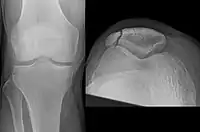

Vertical patella fracture

Some people have a normal bipartite patella or two-part patella which can appear as a fracture. The fragment is usually seen in the top outer corner of the patella and can be distinguished from a fracture by being present in both knees.[6]